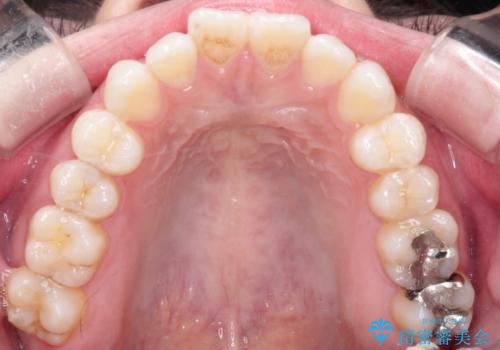

【インビザライン】がたつきをなおしたい

- 上下の前歯の凸凹が気になり、来院されました。

インビザラインで綺麗に仕上がり、満足していただきました。